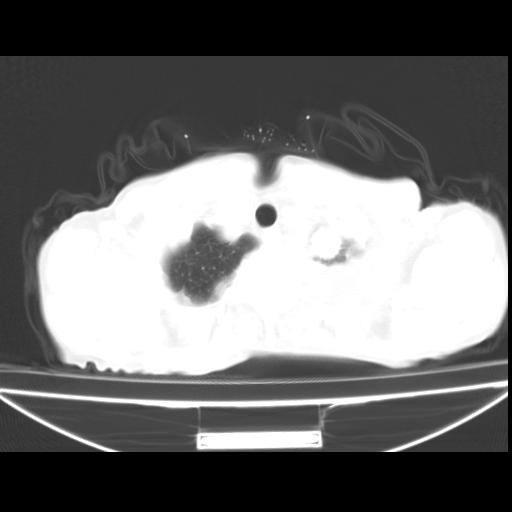

以下是引用随光逐影在2010-3-24 19:15:00的发言:[br]结合病史,考虑双肺及纵隔淋巴结多发转移、左侧胸膜转移并左侧大量胸水,左下肺膨胀不全。

以下是引用zxl51642在2010-3-24 18:49:00的发言:[br]结合乳腺癌术后病史,考虑双肺及纵隔淋巴结多发转移、左侧胸膜转移并左侧大量胸水、左下肺膨胀不全。